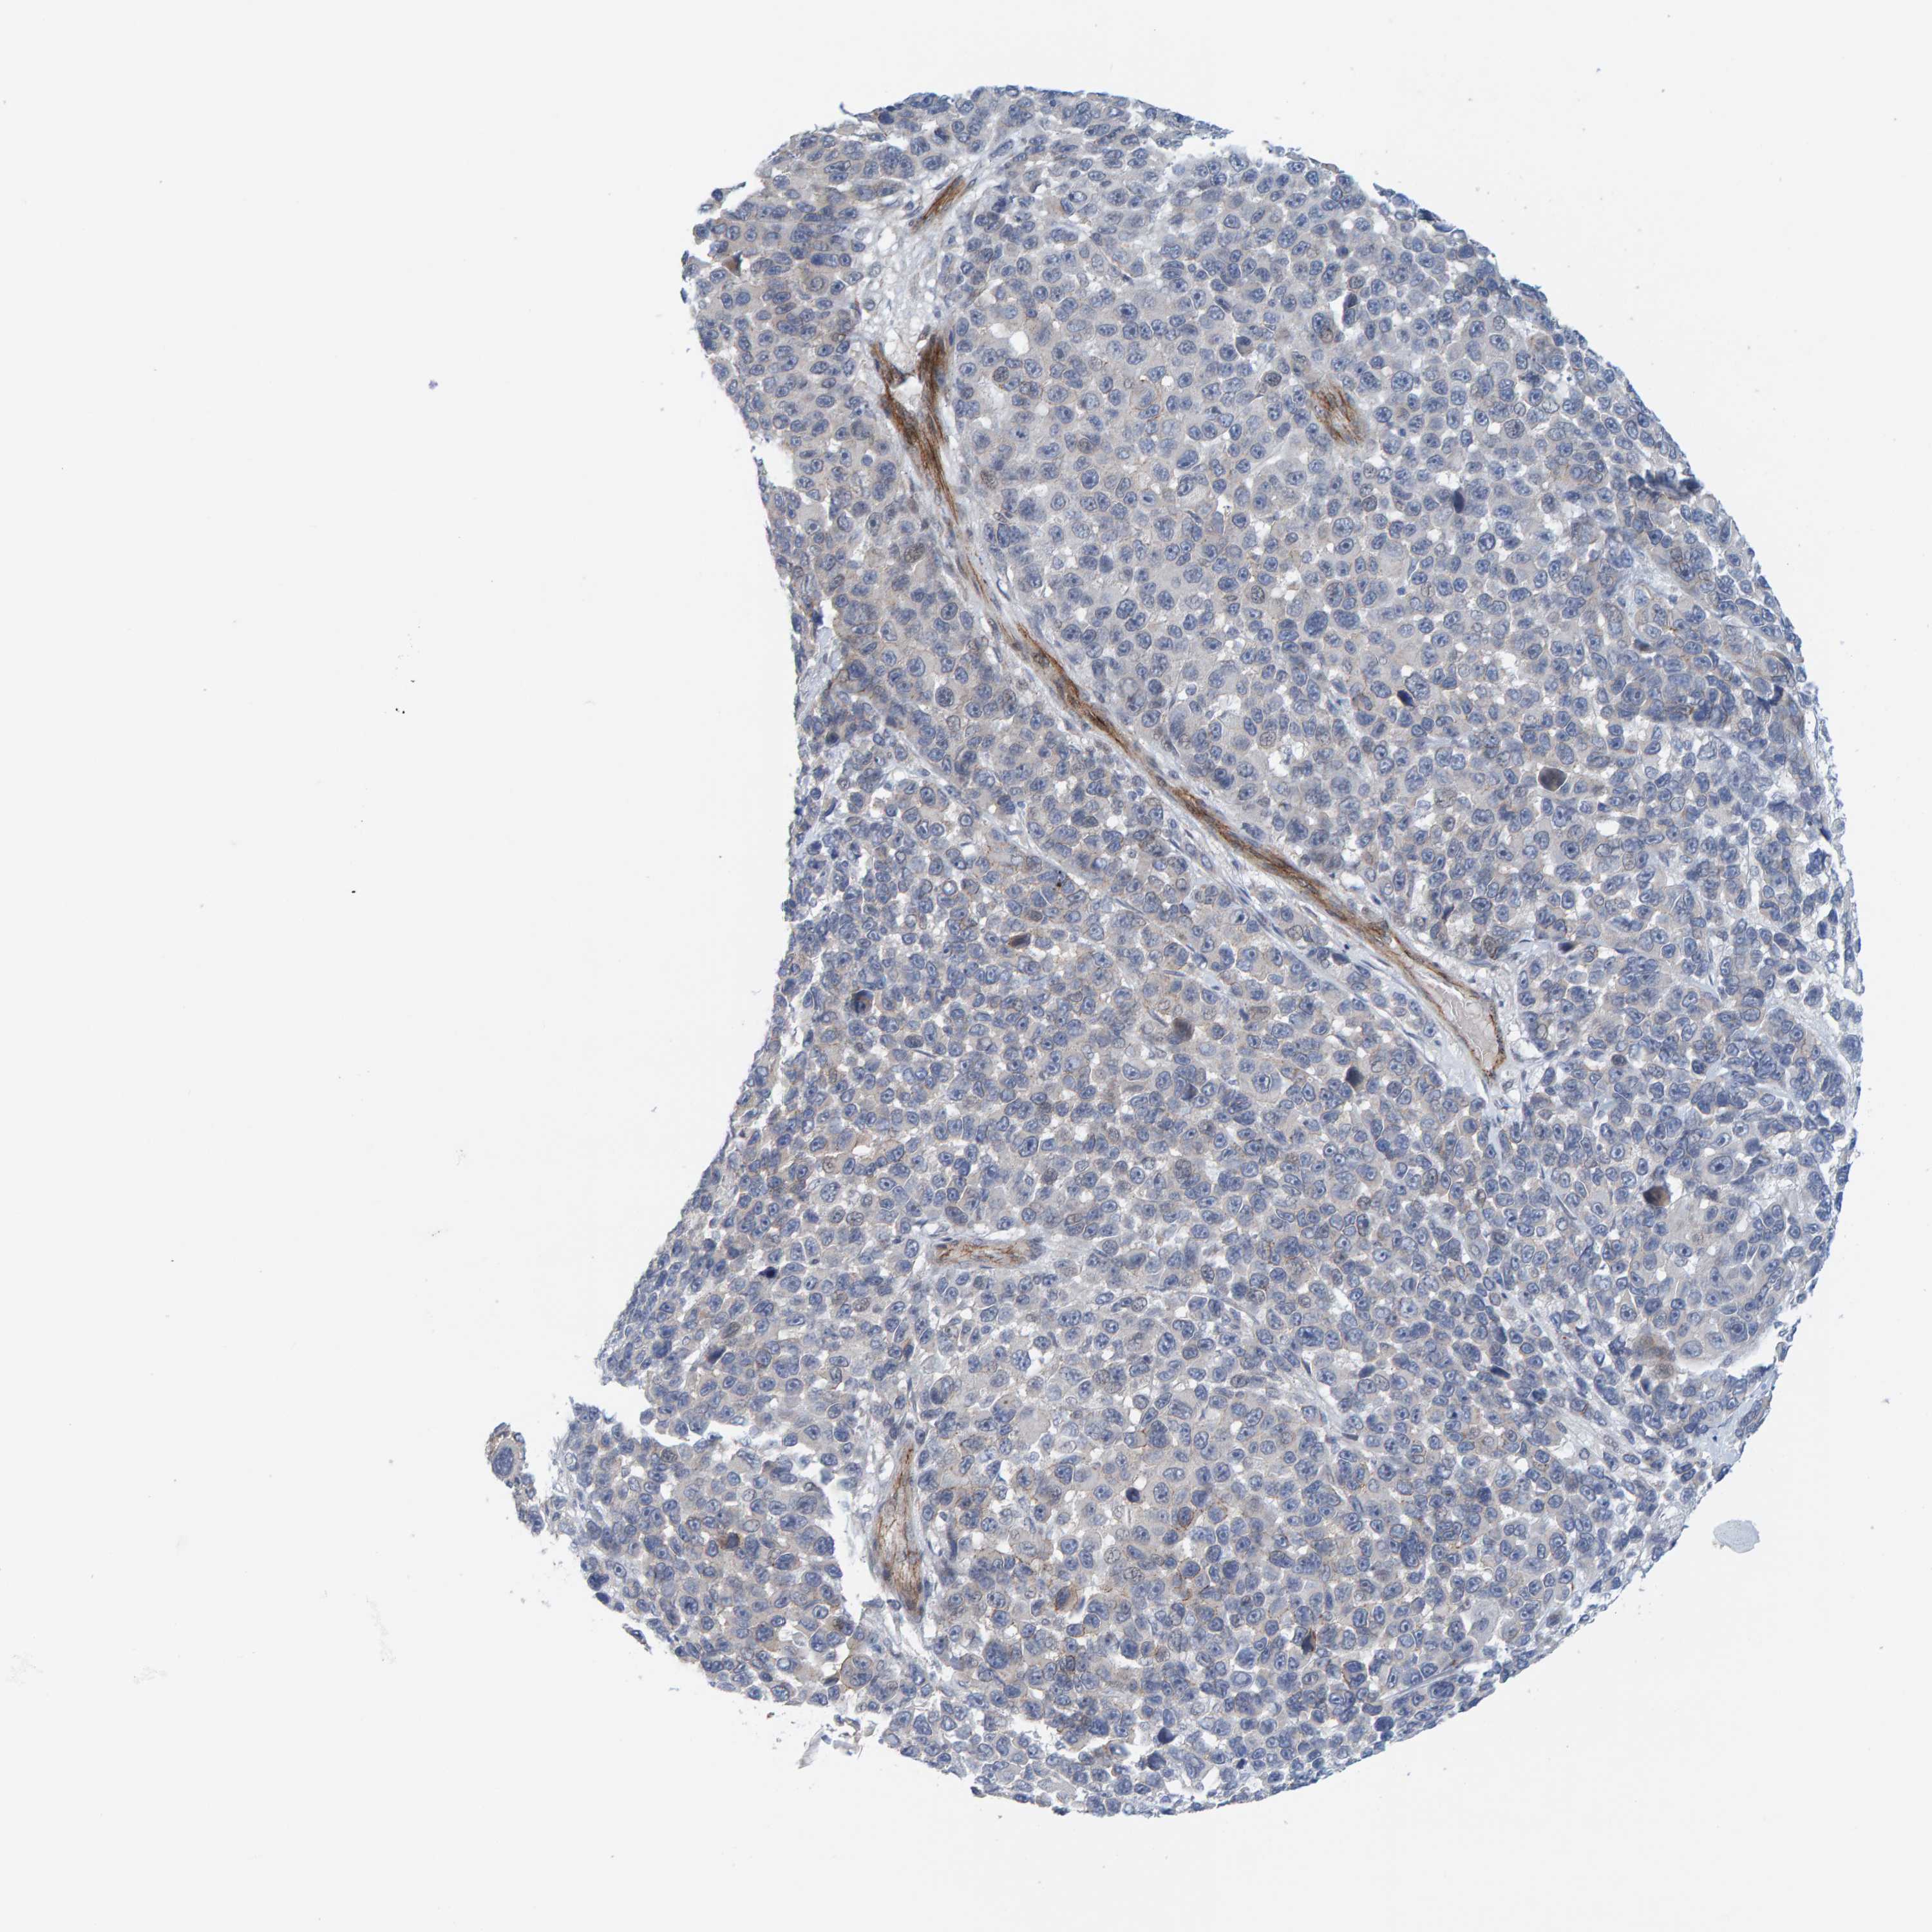

MELANOMA - Protein expressioni

A mouse-over function shows sample information and annotation data. Click on an image to view it in a full screen mode. Samples can be filtered based on level of antibody staining by selecting one or several of the following categories: high, medium, low and not detected. The assay and annotation is described here.

Note that samples used for immunohistochemistry by the Human Protein Atlas do not correspond to samples in the TCGA dataset.

Antibody stainingi

Antibody staining in the annotated cell types in the current human tissue is reported as not detected, low, medium, or high, based on conventional immunohistochemistry profiling in selected tissues. This score is based on the combination of the staining intensity and fraction of stained cells.

Each image is clickable and will lead to virtual microscopy that enables deeper exploration of all samples and also displays staining intensity scores, fraction scores and subcellular localization as well as patient and tissue information for each sample.

Antibody HPA022849

Staining

High

Medium

Low

Not detected

Intensity

Strong

Moderate

Weak

Negative

Quantity

>75%

75%-25%

<25%

None

Location

Nuclear

Cytoplasmic/membranous

Cytoplasmic/membranous,nuclear

Malignant melanoma, NOS

Malignant melanoma, Metastatic site